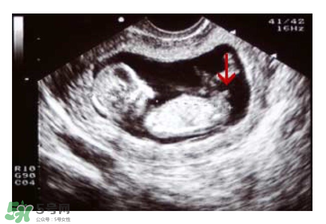

媽媽們可以在懷孕兩個(gè)月的時(shí)候去做B超,如果寶寶的形狀是長(zhǎng)型的,像茄子或長(zhǎng)條狀的,那么很有可能是男寶寶,若是橢圓或是圓型,那么可能是女寶寶。

NT超圖全景看寶寶性別,親證有效的B超自測(cè)男女方法

如果媽媽是孕晚期,也可以看B超圖,對(duì)著你的,一般是女寶寶,背著的,一般是男寶寶。